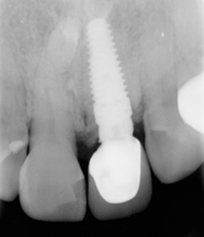

假牙拆除前的X光片,可看出假牙已不密合